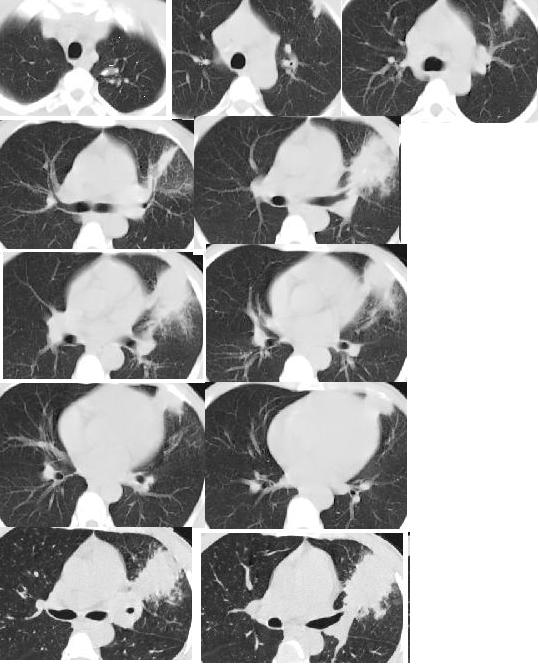

以下是引用随光逐影在2008-9-4 22:33:00的发言:[br]考虑左肺上叶舌段周围型肺癌并阻塞性肺炎,左肺门及纵隔淋巴结转移。

以下是引用huangxun4321在2008-9-4 22:06:00的发言:[br]肿块不规则,内可见坏死液化,边缘可见毛刺征,周围可见晕征,胸膜牵拉征,临床有痰中带血,考虑周围型肺癌可能性大